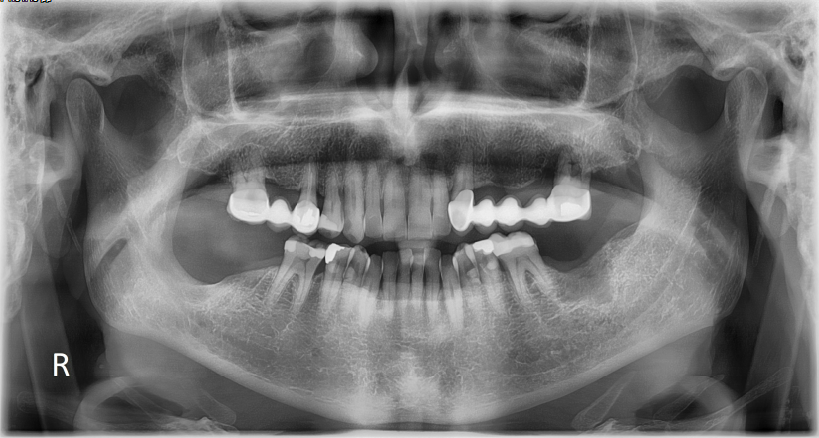

Μετά την επιτυχή χειρουργική αντιμετώπιση της βλάβης ο ασθενής τέθηκε σε 6μηνιαίο απεικονιστικό επανέλεγχο με πανοραμική ακτινογραφία.

Σε κάθε επανεξέταση παρατηρούνταν το παραμένον οστικό έλλειμμα στη θέση της προϋπάρχουσας βλάβης το οποίο είχε ομαλά όρια χωρίς την παρουσία πλέον παθολογικών ευρημάτων.

Πανοραμική Ακτινογραφία 09/2021

Πανοραμική Ακτινογραφία 03/2022